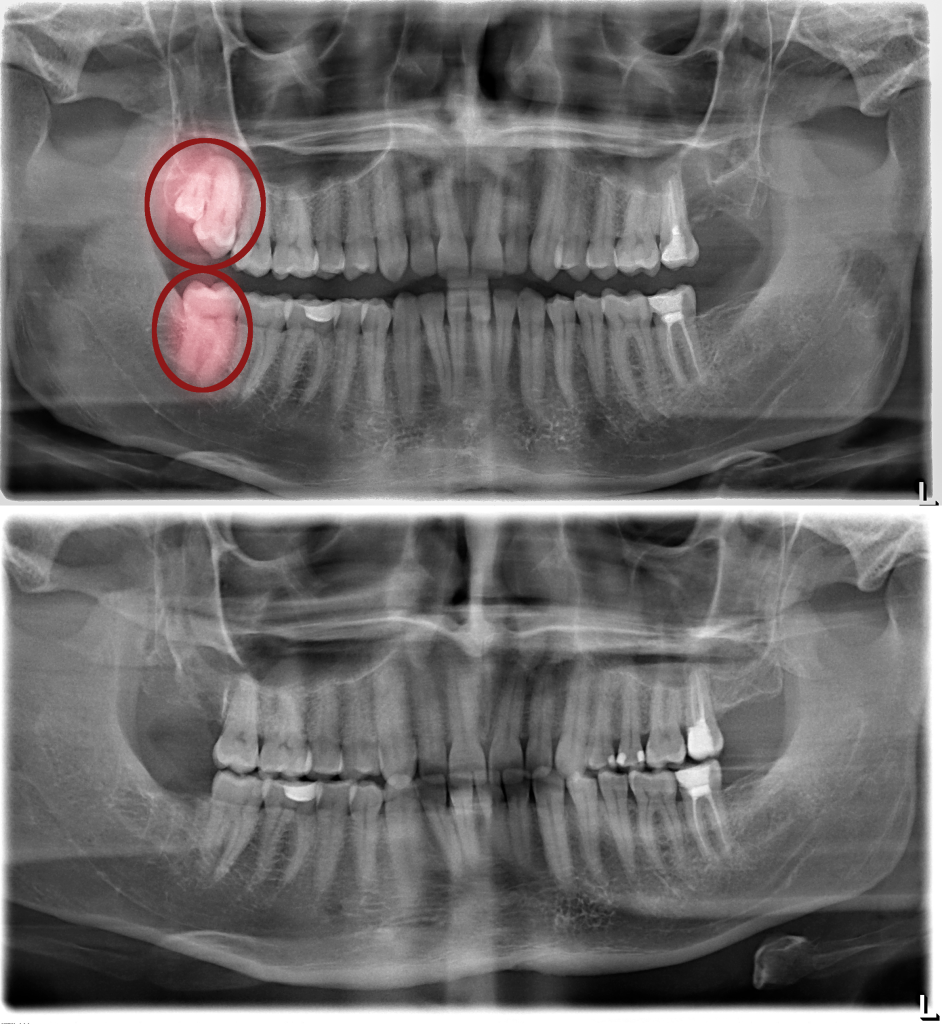

Sebelum & Sesudah Tindakan (Before – After)

Sumber: https://santarosaoralsurgery.com/wp-content/uploads/2021/08/santa-rosa-impaction-bracketing-1.jpeg